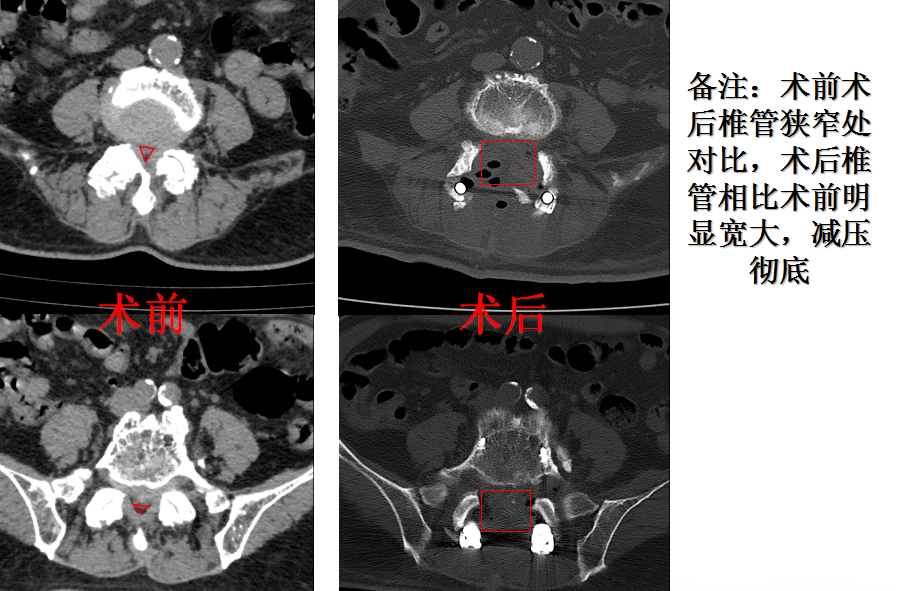

住院后,骨四科(脊柱外科)主任、主任医师姜树东带领全科医师讨论李大爷的病情,考虑李大爷自身疾病特点,双节段重度腰椎管狭窄、腰椎间盘突出,已经超出微创所能解决的范畴,具备开放手术指征。完善相关术前检查后及手术准备后,刘正详细与家属及本人交代手术情况及风险,家属及本人认同手术风险、同意手术。

住院第3天,由姜树东主刀,刘正和骨四科(脊柱外科)医师梁得华协助,共同为李大爷进行了手术。手术中,姜树东利用骨科机器人精确定位、超声骨刀削骨如泥,让手术更佳得心应手。术中医生发现,李大爷不光腰椎椎管狭窄、脊髓神经压迫严重,连后方椎管外也增生了厚厚的一层骨赘,最厚处达1cm,这给手术带来了挑战,所幸姜树东经验丰富、技艺精湛,刘正、梁得华配合得当,对李大爷的受压脊髓、神经进行了彻底减压,手术顺利。术后李大爷平安回到病房。